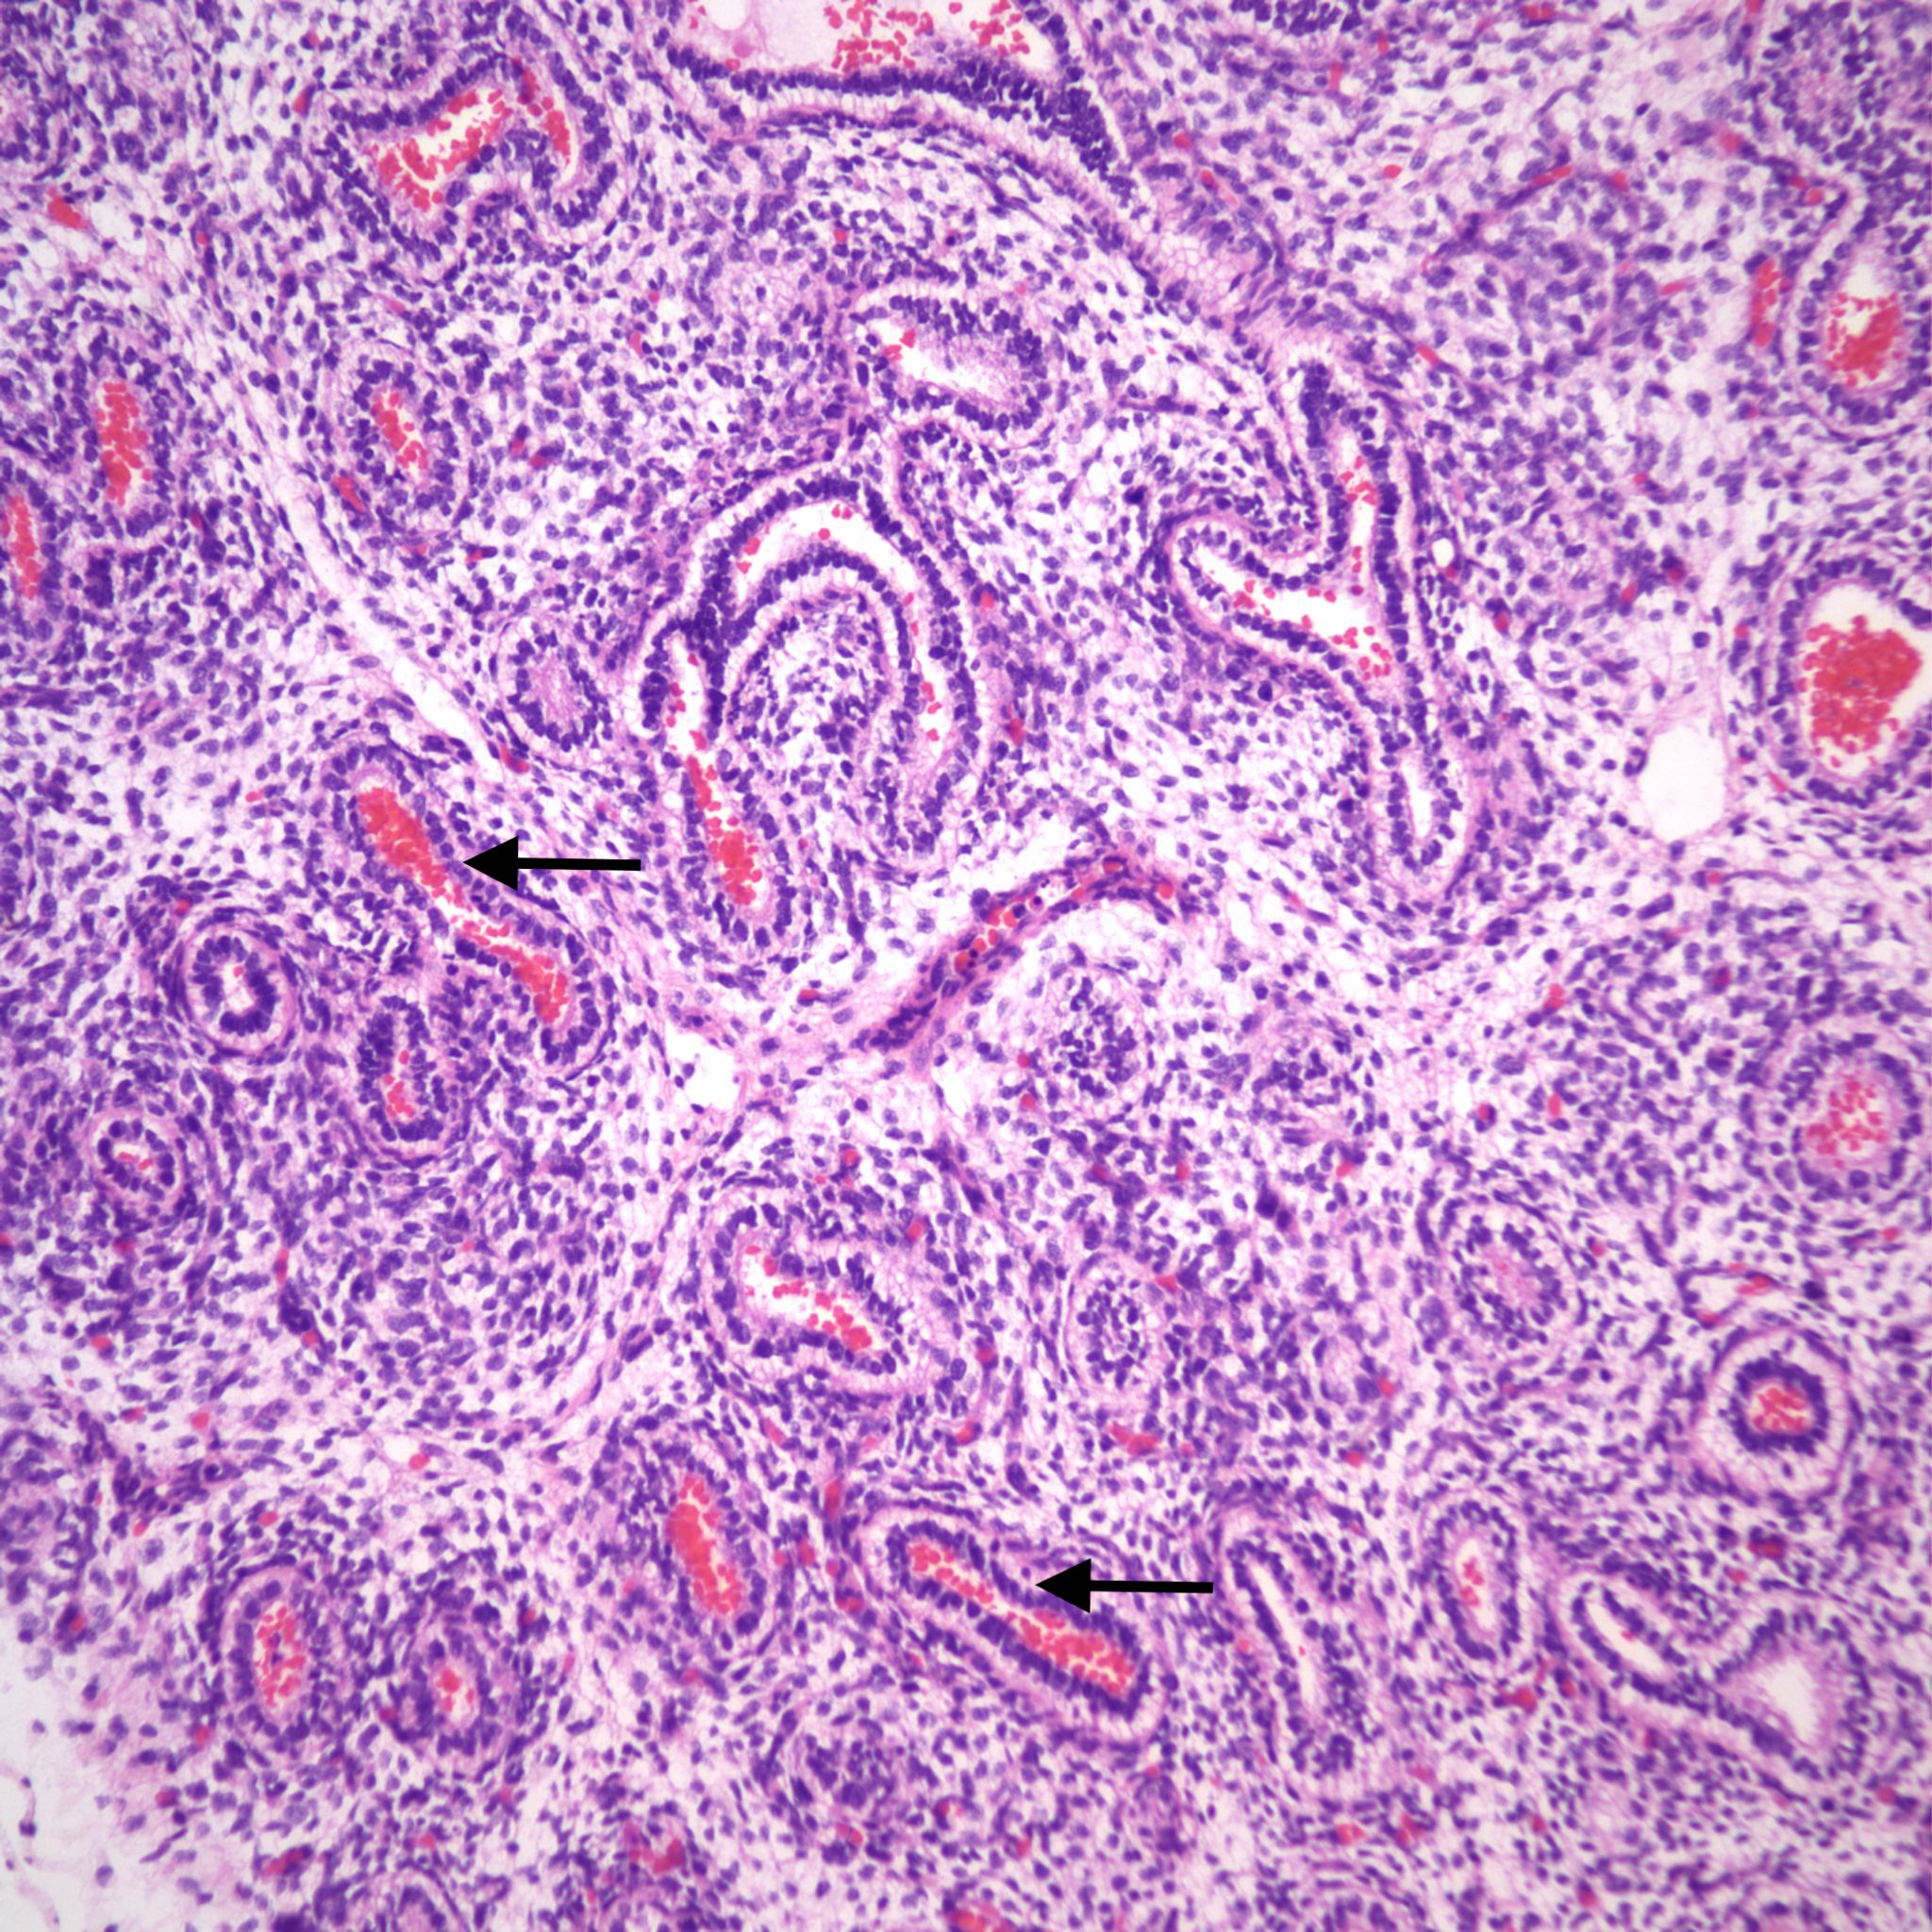

However, the karyorhectic cells lack the intact cytoplasm of neutrophils. It is not possible to observationally determine whether neutrophils in the airway are from aspiration of neutrophils in the amniotic fluid, or are from fetal neutrophils in response to aspirated bacteria. The exception is with focal bronchopneumonia which demonstrates a fetal inflammatory response with large, focal accumulations of neutrophils and vasodilatation of surrounding capillaries (fig 12a,b).

It is conceivable that bacteria can travel through the fetal airways after fetal death, but neutrophils in the lungs and gastrointestinal tract are presumed evidence of chorioamnionitis in the living fetus. Overgrowth of bacteria may be directly observable in the airways. Some organisms in stillbirth without postmortem retention, such as Group B beta hemolytic streptococcus show such overgrowth in the living fetus, while in other cases the bacterial overgrowth is likely postmortem (even if initially present in life), especially for organisms adapted to low environmental oxygen (Fig 13).